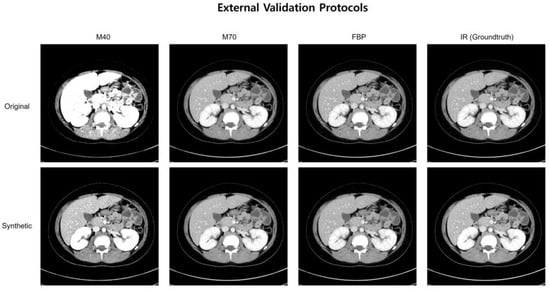

| Reconstruction methods | FBP, IR, M40, M60, M80, OPT † | FBP, IR, M40, M70 † |

| External Validation | ||||||

| Original | 75 (19%) | 68 (18%) | 55 (14%) | 59 (15%) | 92 (24%) | 369 (95%) |

| Synthetic | 199 (51%) | 239 (62%) | 266 (69%) | 244 (63%) | 212 (55%) | 365 (94%) |

| Increase (%) | 32% | 44% | 55% | 48% | 31% | −1% |